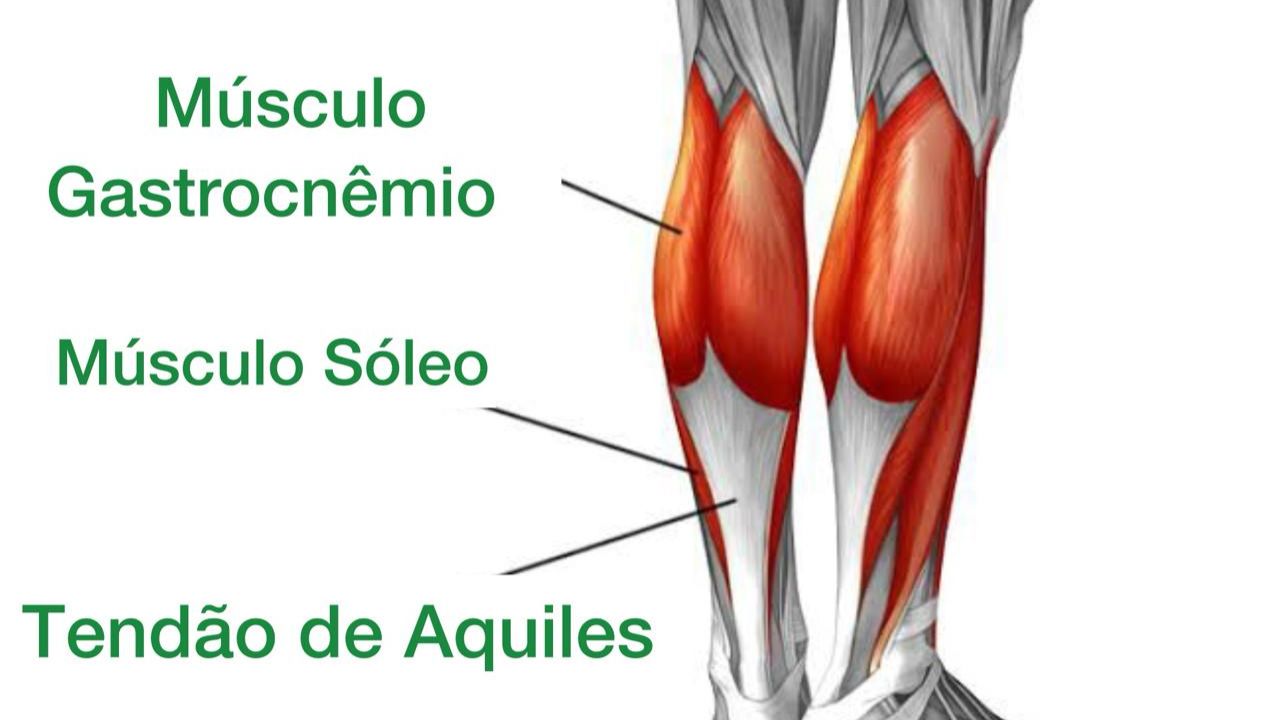

O tratamento inicial segue o protocolo de repouso, aplicação de gelo para reduzir a inflamação e, se necessário, o uso de anti-inflamatórios. A fisioterapia é crucial e foca em exercícios específicos de alongamento e, principalmente, de fortalecimento excêntrico da panturrilha, que comprovadamente ajudam na recuperação do tendão. O uso de calcanheiras de silicone pode aliviar a tensão temporariamente.

Para prevenir a tendinite de Aquiles, o segredo é a progressão gradual nas atividades físicas. Aumente a intensidade e a distância dos treinos aos poucos. Dedique tempo para alongar e fortalecer os músculos da panturrilha regularmente. E, claro, use sempre tênis adequados para o seu tipo de pisada e para o esporte que você pratica.